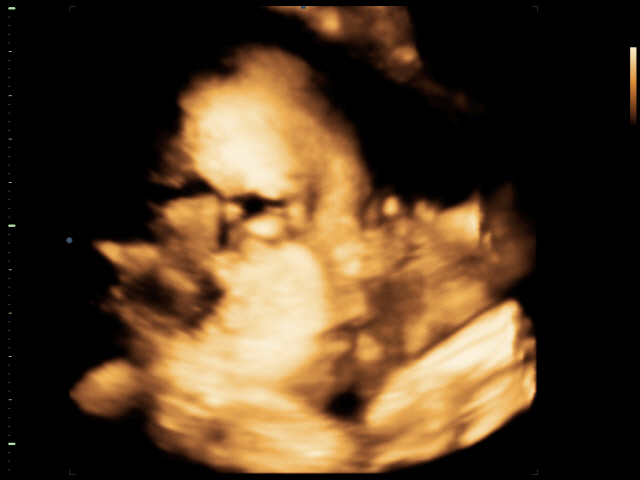

Miči{{_AND_}}Riči